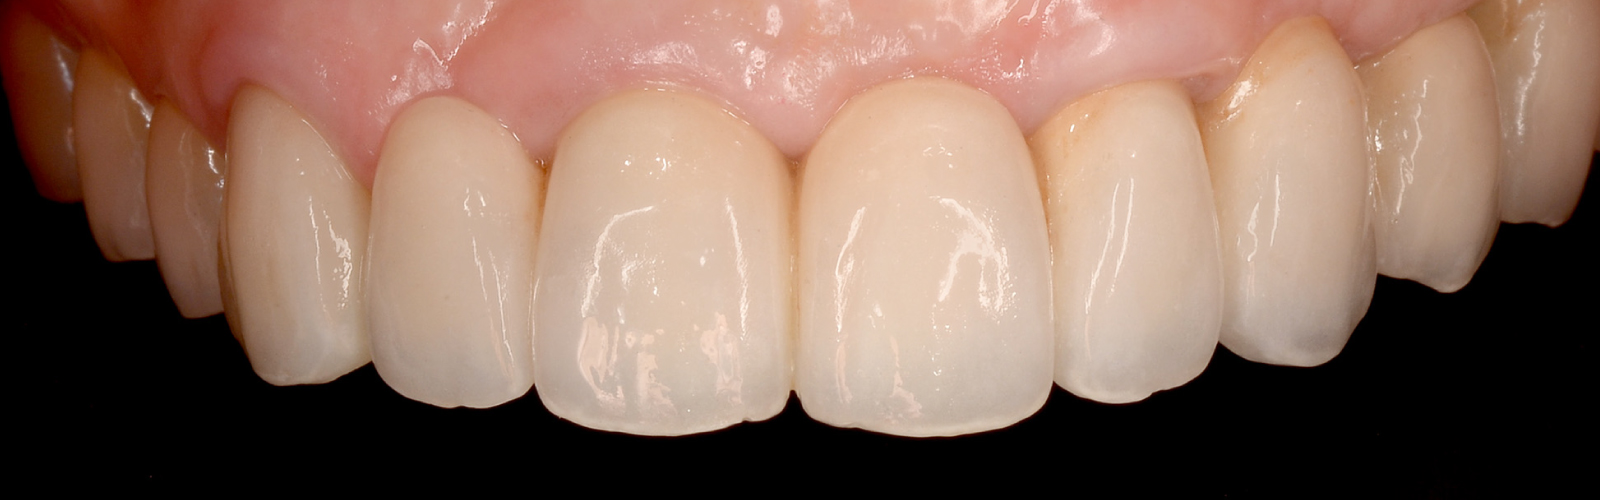

とびきり美しい上部構造

ただ治すのではなく、美しく治す。しかも、とびっきり美しく治すことにこだわっています。そのため、数々の賞を受賞する腕の良い歯科技工士と連携して歯をデザインしています。